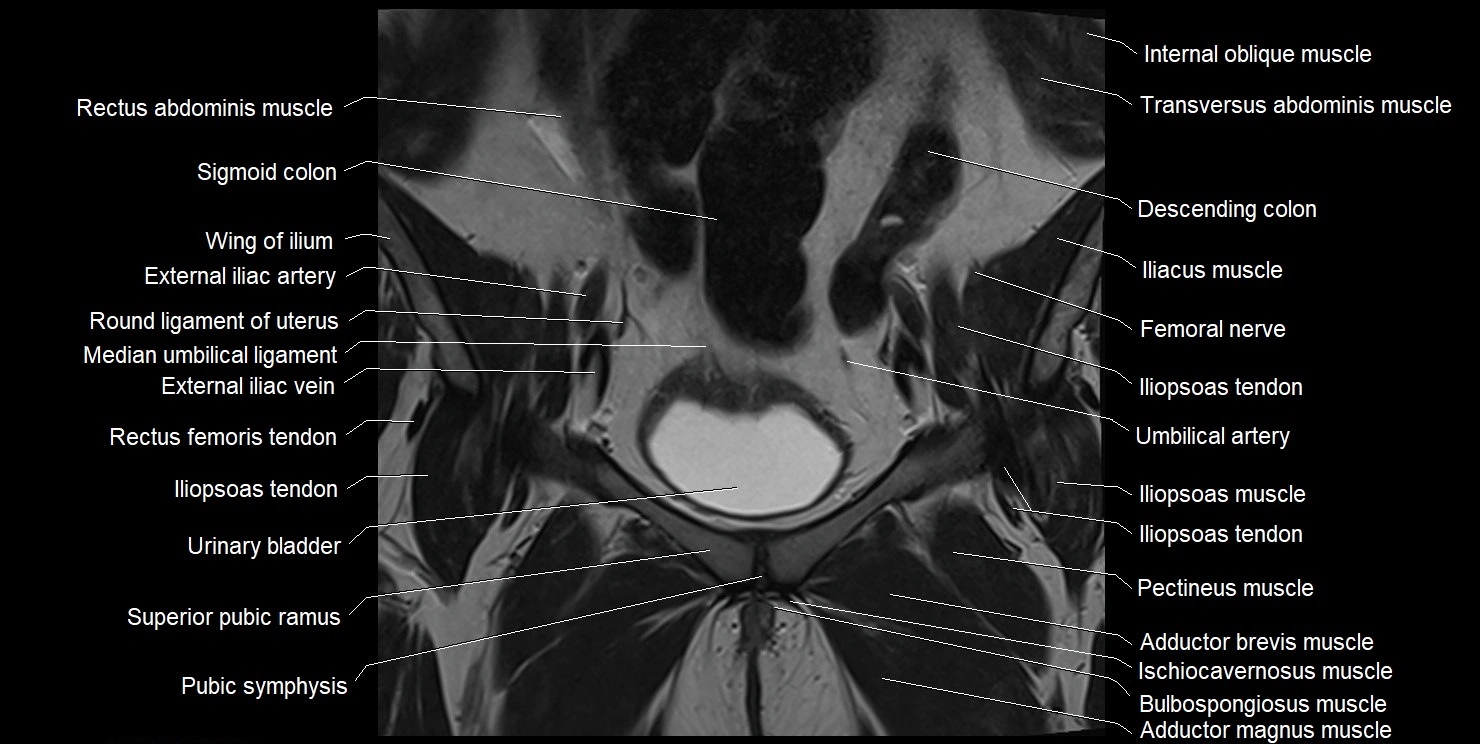

- Adductor brevis muscle

- Adductor magnus muscle

- External iliac artery

- External iliac vein

- Femoral nerve

- Iliopsoas muscle

- Iliopsoas tendon

- Internal oblique muscle

- Linea alba

- Median umbilical ligament

- Pectineus muscle

- Pubic symphysis

- Rectus femoris muscle

- Rectus femoris tendon (Proximal tendon of rectus femoris)

- Round ligament of uterus

- Sigmoid colon

- Superior pubic ramus

- Transversus abdominis muscle